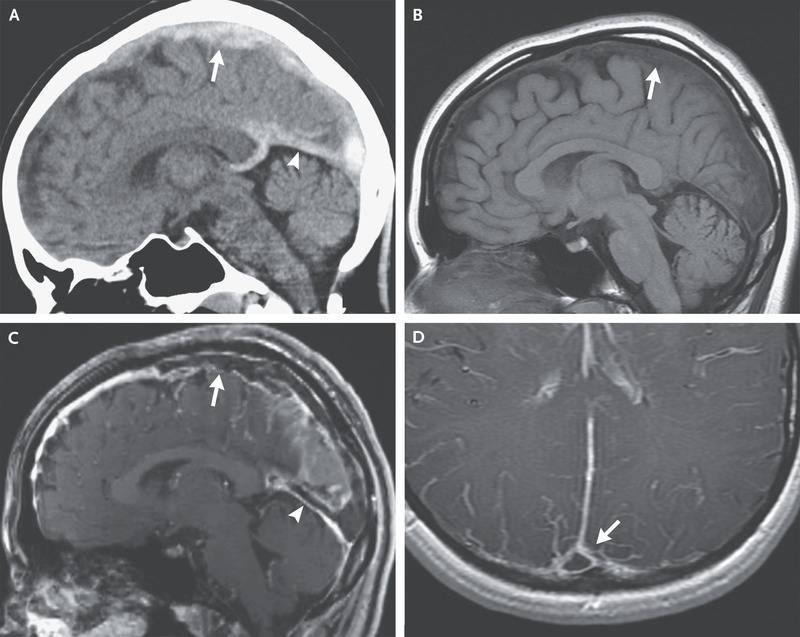

Um die Diagnose einer Hirnvenenthrombose zu sichern, kann die Durchführung einer Magnetresonanztomographie (MRT) mit einer venösen Angiographie (MRA) helfen. Sie ist die Methode erster Wahl bei der Diagnostik und Verlaufskontrolle von Hirnvenenthrombosen.

Die Auswertung eines MRT Befundes erweist sich im Rahmen einer Hirnvenenthrombose als sehr komplex. Dies ist darin begründet, dass das Signal vom Alter des Thrombus abhängig ist.

Alternativ bietet sich die Computertomographie (CT) an. Die zerebrale Computertomographie kommt häufig in der Primärdiagnostik zum Einsatz. Sie kann dabei helfen, erste Hinweise einer Hirnvenenthrombose zu liefern und ist daher von praktischer Bedeutung.

Die alleinige Anwendung der zerebralen Computertomographie genügt jedoch nicht, um die Diagnose einer Hirnvenenthrombose sicher zu beweisen.3

Neben der konventionellen Anwendung der Computertomographie bietet sich ferner die Durchführung einer Computertomographie mit einer venösen Angiographie an. Bei der sogenannten CT-Venographie lassen sich durch die Verabreichung von Kontrastmitteln die kortikalen Venen, Brückenvenen und Sinus darstellen.

Die CT-Venographie stellt somit ein gutes alternatives nichtinvasives Verfahren im Vergleich zur Magnetresonanzangiographie dar. Die kurzen Untersuchungszeiten und die geringere Anfälligkeit von Artefakten sind vorteilhaft. Von Nachteil sind jedoch die Anwendung von Kontrastmittel sowie die Strahlenbelastung durch Röntgenstrahlung.

Beide Verfahren dienen dazu, in Sinus oder/und Vene den Thrombus zu identifizieren. Stauungsbedingte Ödeme, Ischämien oder Blutungen lassen sich bei Bedarf ebenfalls lokalisieren.